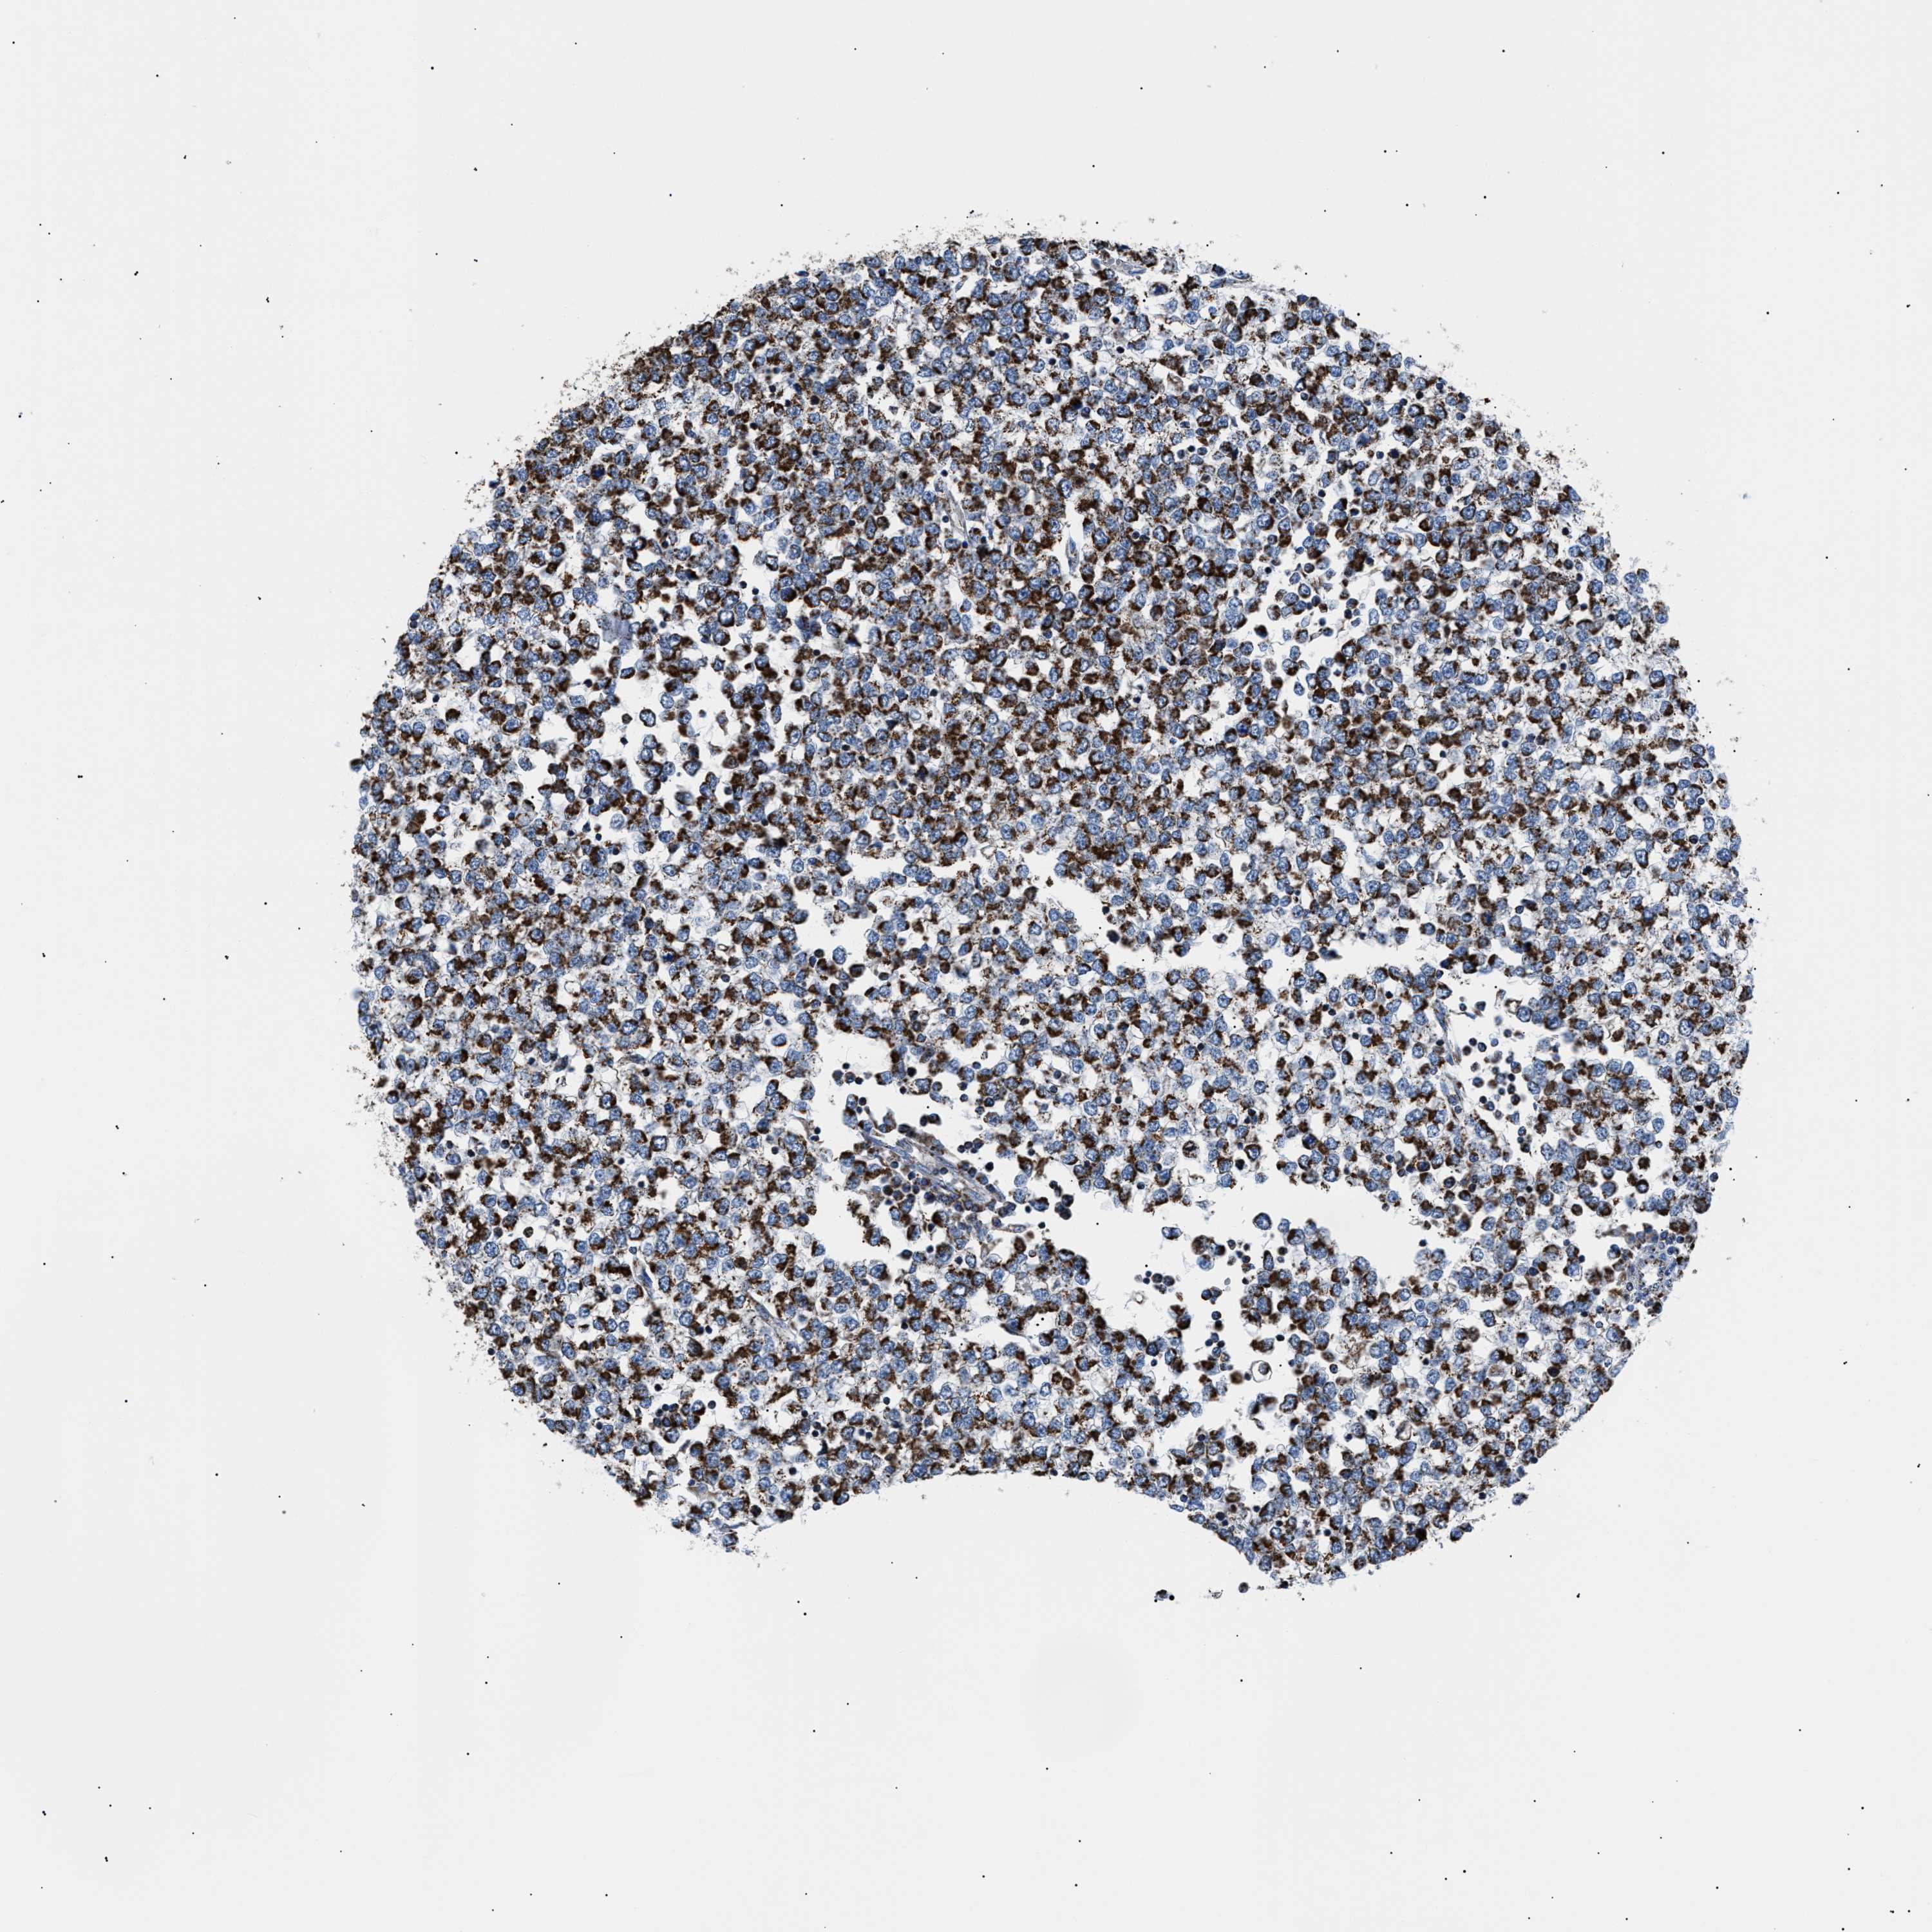

TESTIS CANCER - Protein expressioni

A mouse-over function shows sample information and annotation data. Click on an image to view it in a full screen mode. Samples can be filtered based on level of antibody staining by selecting one or several of the following categories: high, medium, low and not detected. The assay and annotation is described here.

Note that samples used for immunohistochemistry by the Human Protein Atlas do not correspond to samples in the TCGA dataset.

Antibody stainingi

Antibody staining in the annotated cell types in the current human tissue is reported as not detected, low, medium, or high, based on conventional immunohistochemistry profiling in selected tissues. This score is based on the combination of the staining intensity and fraction of stained cells.

Each image is clickable and will lead to virtual microscopy that enables deeper exploration of all samples and also displays staining intensity scores, fraction scores and subcellular localization as well as patient and tissue information for each sample.

Antibody HPA039874

Carcinoma, Embryonal, NOS

Seminoma, NOS